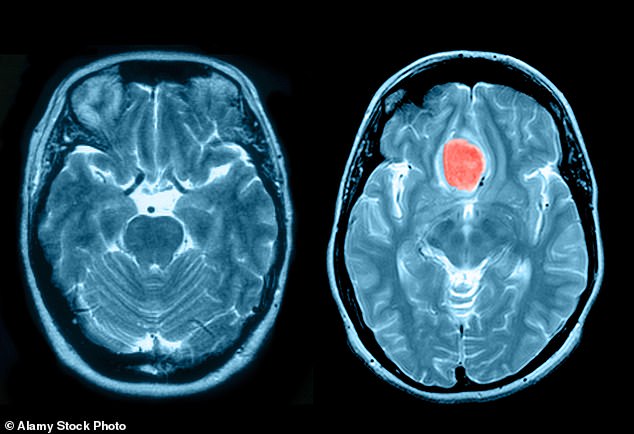

Study reveals that birth control used by many raises the risk of brain tumors

Women using a popular contraceptive injection face a heightened risk of developing potentially fatal brain tumors, according to a new study. This marks the third significant investigation in a little over a year that suggests the contraceptive, which increases the likelihood of meningioma— the most prevalent form of brain tumor— particularly in those who’ve been […]